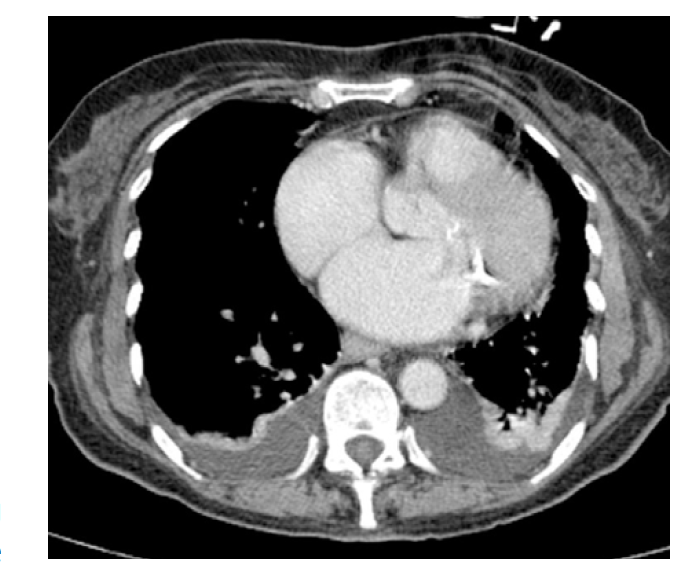

What is this?

IMH